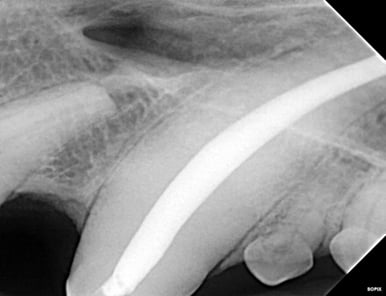

Below: During RCT - Radiograph finding working length to clean and measure canal

%20-%20March%202024/during%20RCT%20-%20finding%20working%20length.jpg?width=379&height=291&name=during%20RCT%20-%20finding%20working%20length.jpg)

Below: During RCT - finding master file size to clean canal walls appropriately and find master cone size of gutta percha

%20-%20March%202024/Radiograph%20of%20master%20file%20during%20RCT.jpg?width=386&height=296&name=Radiograph%20of%20master%20file%20during%20RCT.jpg)